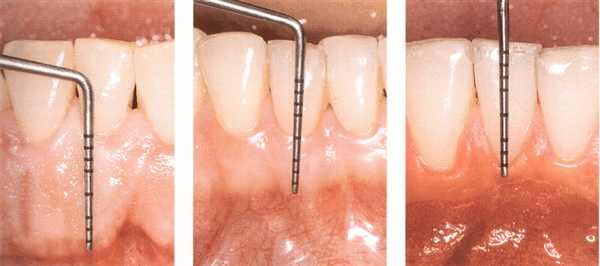

Клинически здоровая десна имеет борозду некоторой глубины. Ее глубина, определенная на гистологических срезах, составляет 1,8 мм, с вариацией от 0 до 6 мм; в других исследованиях сообщалось о 1,5 мм и 0,69 мм. Клиническая оценка, используемая для определения глубины борозды, проводится путем введения металлического инструмента - пародонтального зонда и определения расстояния, на которое он проникает. Гистологически глубина борозды не обязательно должна быть в точности равна глубине проникновения зонда. Так называемая глубина зондирования клинически нормальной десны у людей составляет от 2 до 3 мм.

Десневая борозда представляет собой неглубокую щель или пространство вокруг зуба, ограниченное поверхностью зуба с одной стороны и эпителием, выстилающим свободный край десны, с другой стороны. Она имеет V-образную форму и едва позволяет вводить пародонтальный зонд. Клиническое определение глубины десневой борозды является важным диагностическим показателем. При абсолютно нормальных или идеальных условиях глубина десневой борозды составляет 0 мм или приближается к этому значению. Этого можно достичь экспериментально только у животных, полностью лишенных микроорганизмов, или после интенсивного длительного предупреждения образования бляшек.

Представляет собой узкий желобок, окружающий зуб, глубиной 0,5 мм. Дно десневой борозды образовано клетками соединителньго эпителия, которые быстро слущиваются.